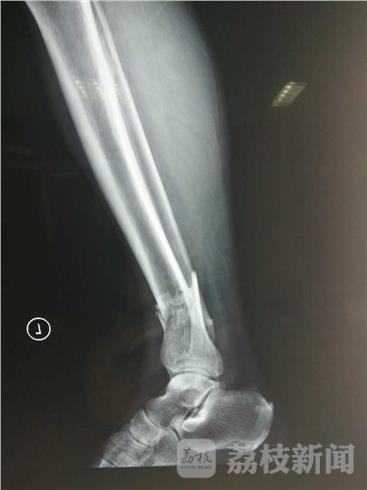

据伤者女婿姚先生介绍,当时自己的老丈人由小区西门出来向南行驶,突然被一辆由北向南的电瓶车撞倒,老丈人被撞后肇事电瓶车肇事逃逸,随后他将老丈人送往医院检查。经诊断,老丈人左脚踝骨折,目前警方正在追查肇事电瓶车。